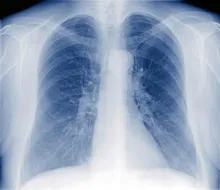

Denver Public Health (DPH) and Metropolitan State University of Denver (MSU Denver) successfully partnered to test the majority of faculty and students who were potentially exposed to tuberculosis (TB) on campus this spring. The authorities did not find any evidence of transmission.

Denver Public Health and Jefferson County Public Health are partnering on a tuberculosis investigation at Victory Montessori in Westminster, CO.

Denver Public Health and Tri-County Health Department successfully collaborated with Aurora Public Schools and Aurora Hills Middle School to test the faculty and students who were potentially exposed to TB last fall.